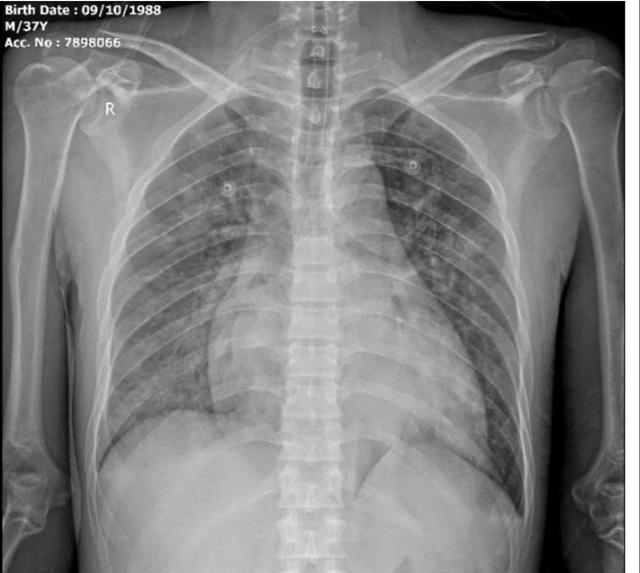

Người bệnh là anh Vi Văn T. (37 tuổi, trú tại xã Tiền Phong, tỉnh Nghệ An), có tiền sử bệnh thận mạn giai đoạn cuối, đang lọc máu chu kỳ nhưng đã bỏ chạy thận khoảng 10 ngày trước khi nhập viện. Khi vào viện, người bệnh trong tình trạng nguy kịch với biểu hiện khó thở dữ dội, ho khạc bọt hồng, phù phổi cấp.

Kết quả xét nghiệm cho thấy nồng độ kali máu tăng rất cao (K⁺ = 9,21 mmol/L), kèm theo biến đổi điện tim rõ rệt - dấu hiệu báo động nguy cơ rối loạn nhịp và ngừng tim đột ngột. Các bác sĩ chẩn đoán xác định: tăng kali máu mức độ nặng, phù phổi cấp, suy tim trên nền bệnh thận mạn giai đoạn 5.